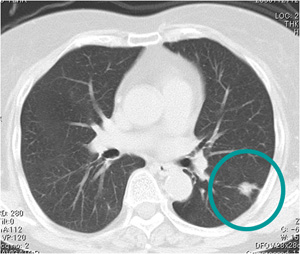

近年、胸部CTで「すりガラス陰影(ground-glass opacity: GGO, ground-glass nodule: GGN)」を呈する腺がん症例が増加しています。肺の末梢部に発生しやすい肺がんで、近年増えてきて肺がん全体の60%程度を占めるようになっており、特に非喫煙者の女性に多い組織型です。

肺腺がん 胸部CT所見

末梢型小型肺腺がんに対しては、予後を考慮した野口分類が日本では広く使われてきて、現在も一部で用いられています。野口Type A, Type Bは早期肺がん例であり、切除後は良好な予後が期待されます。

すりガラス陰影(ground-glass opacity: GGO)を呈する肺腺がん 胸部CT所見